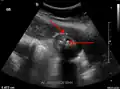

Right upper quadrant abdominal ultrasound is most commonly used to diagnose cholecystitis.[1][26][27] Ultrasound findings suggestive of acute cholecystitis include gallstones, pericholecystic fluid (fluid surrounding the gallbladder), gallbladder wall thickening (wall thickness over 3 mm),[28] dilation of the bile duct, and sonographic Murphy's sign.[13] Given its higher sensitivity, hepatic iminodiacetic acid (HIDA) scan can be used if ultrasound is not diagnostic.[13][14] CT scan may also be used if complications such as perforation or gangrene are suspected.[14]

29. 1 2 "UOTW #30 - Ultrasound of the Week". Ultrasound of the Week. 23 December 2014. Archived from the original on 9 May 2017. Retrieved 27 May 2017.